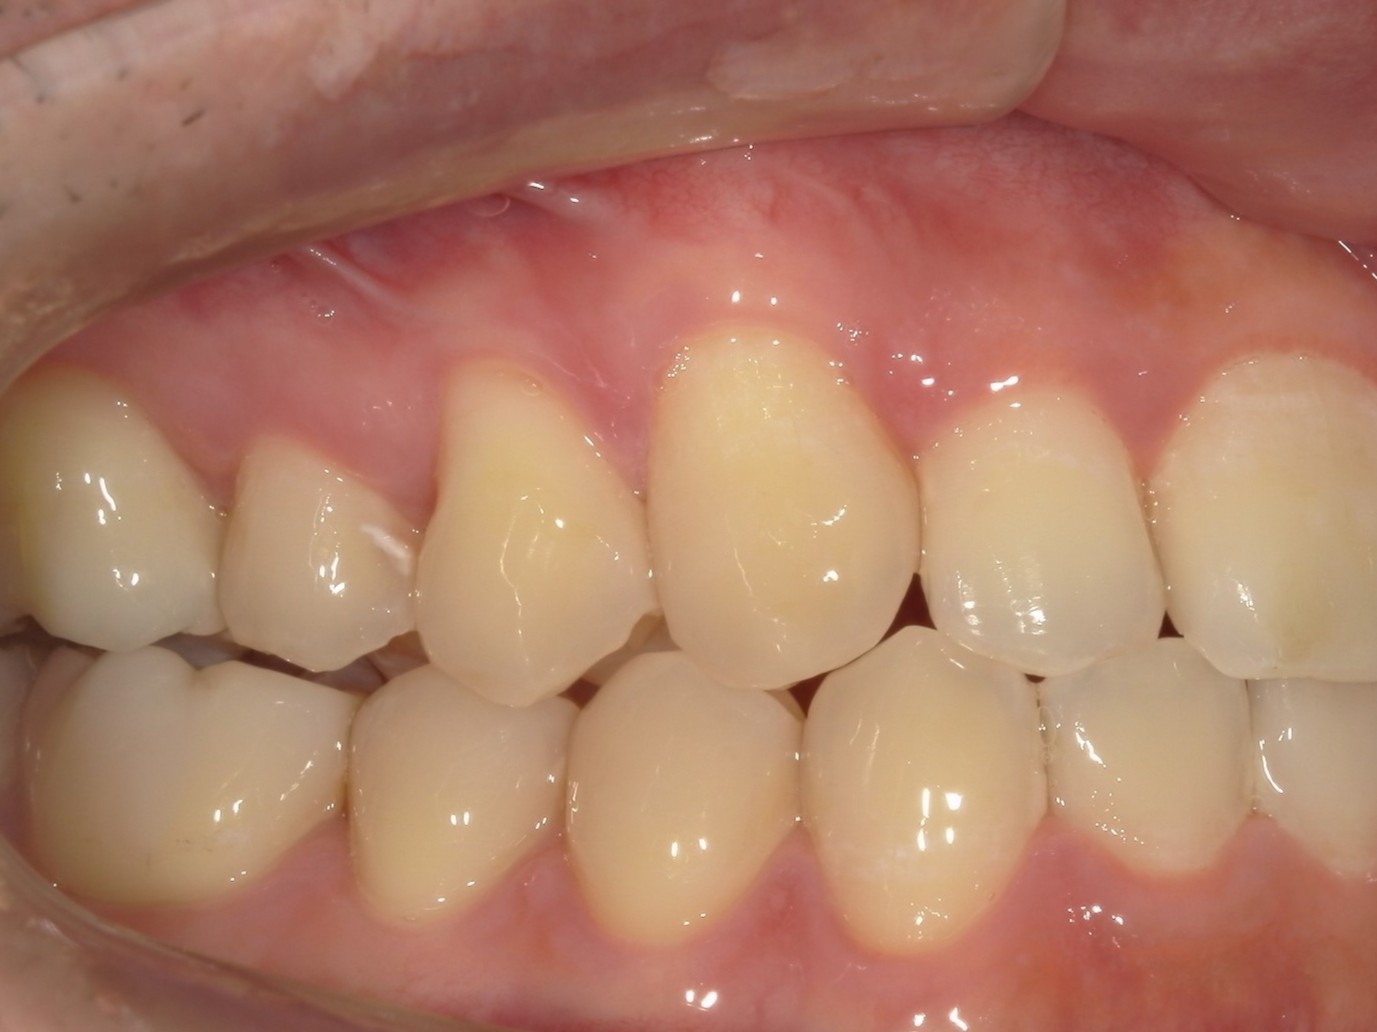

20代男性の方で、叢生・全体的な歯並び(不揃い・ガタガタ・不正咬合)が気になる患者様です。

歯が重なり合う状態は、見た目の問題だけではなく歯磨きが難しくなり虫歯や歯周病を引き起こすリスクにもなるため、インビザライン(重程度)矯正を行いました。

治療前